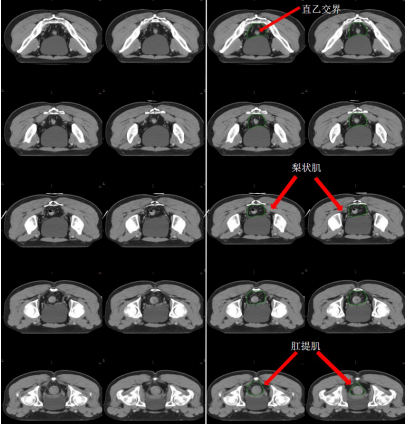

b) 直腸系膜區(qū)-M(深綠) (圖 7),邊界:

上界:腸系膜下動脈分叉為乙狀結(jié)腸動脈與直腸上動脈處/直乙交界;

下界:肛提肌插入外括約肌處/直腸周圍系膜脂肪組織消失處;

前界上:直腸上動脈前緣擴(kuò) 0.7 cm;

前界中/下:直腸系膜筋膜,前方盆腔器官的后界;

后界:盆腔骶前區(qū)的前界;

外界上:側(cè)方、髂外淋巴結(jié)區(qū)的內(nèi)側(cè);

外界中:直腸系膜筋膜,側(cè)方淋巴結(jié)區(qū)的內(nèi)側(cè);

外界下:肛提肌內(nèi)側(cè)緣。

圖 7 直腸癌直腸系膜區(qū) CTV 勾畫示例

h) 肛門括約肌復(fù)合體-SC(桔色) (圖 13)邊界:

上界:肛提肌插入肛門外括約肌處/直腸肛管交界處;

下界:放松位的肛門緣;

前界、后界、內(nèi)界、外界:肛門外括約肌圍成。

圖 12 直腸癌坐骨直腸窩 CTV 勾畫示例

圖 13 直腸癌肛門括約肌復(fù)合體 CTV 勾畫示例